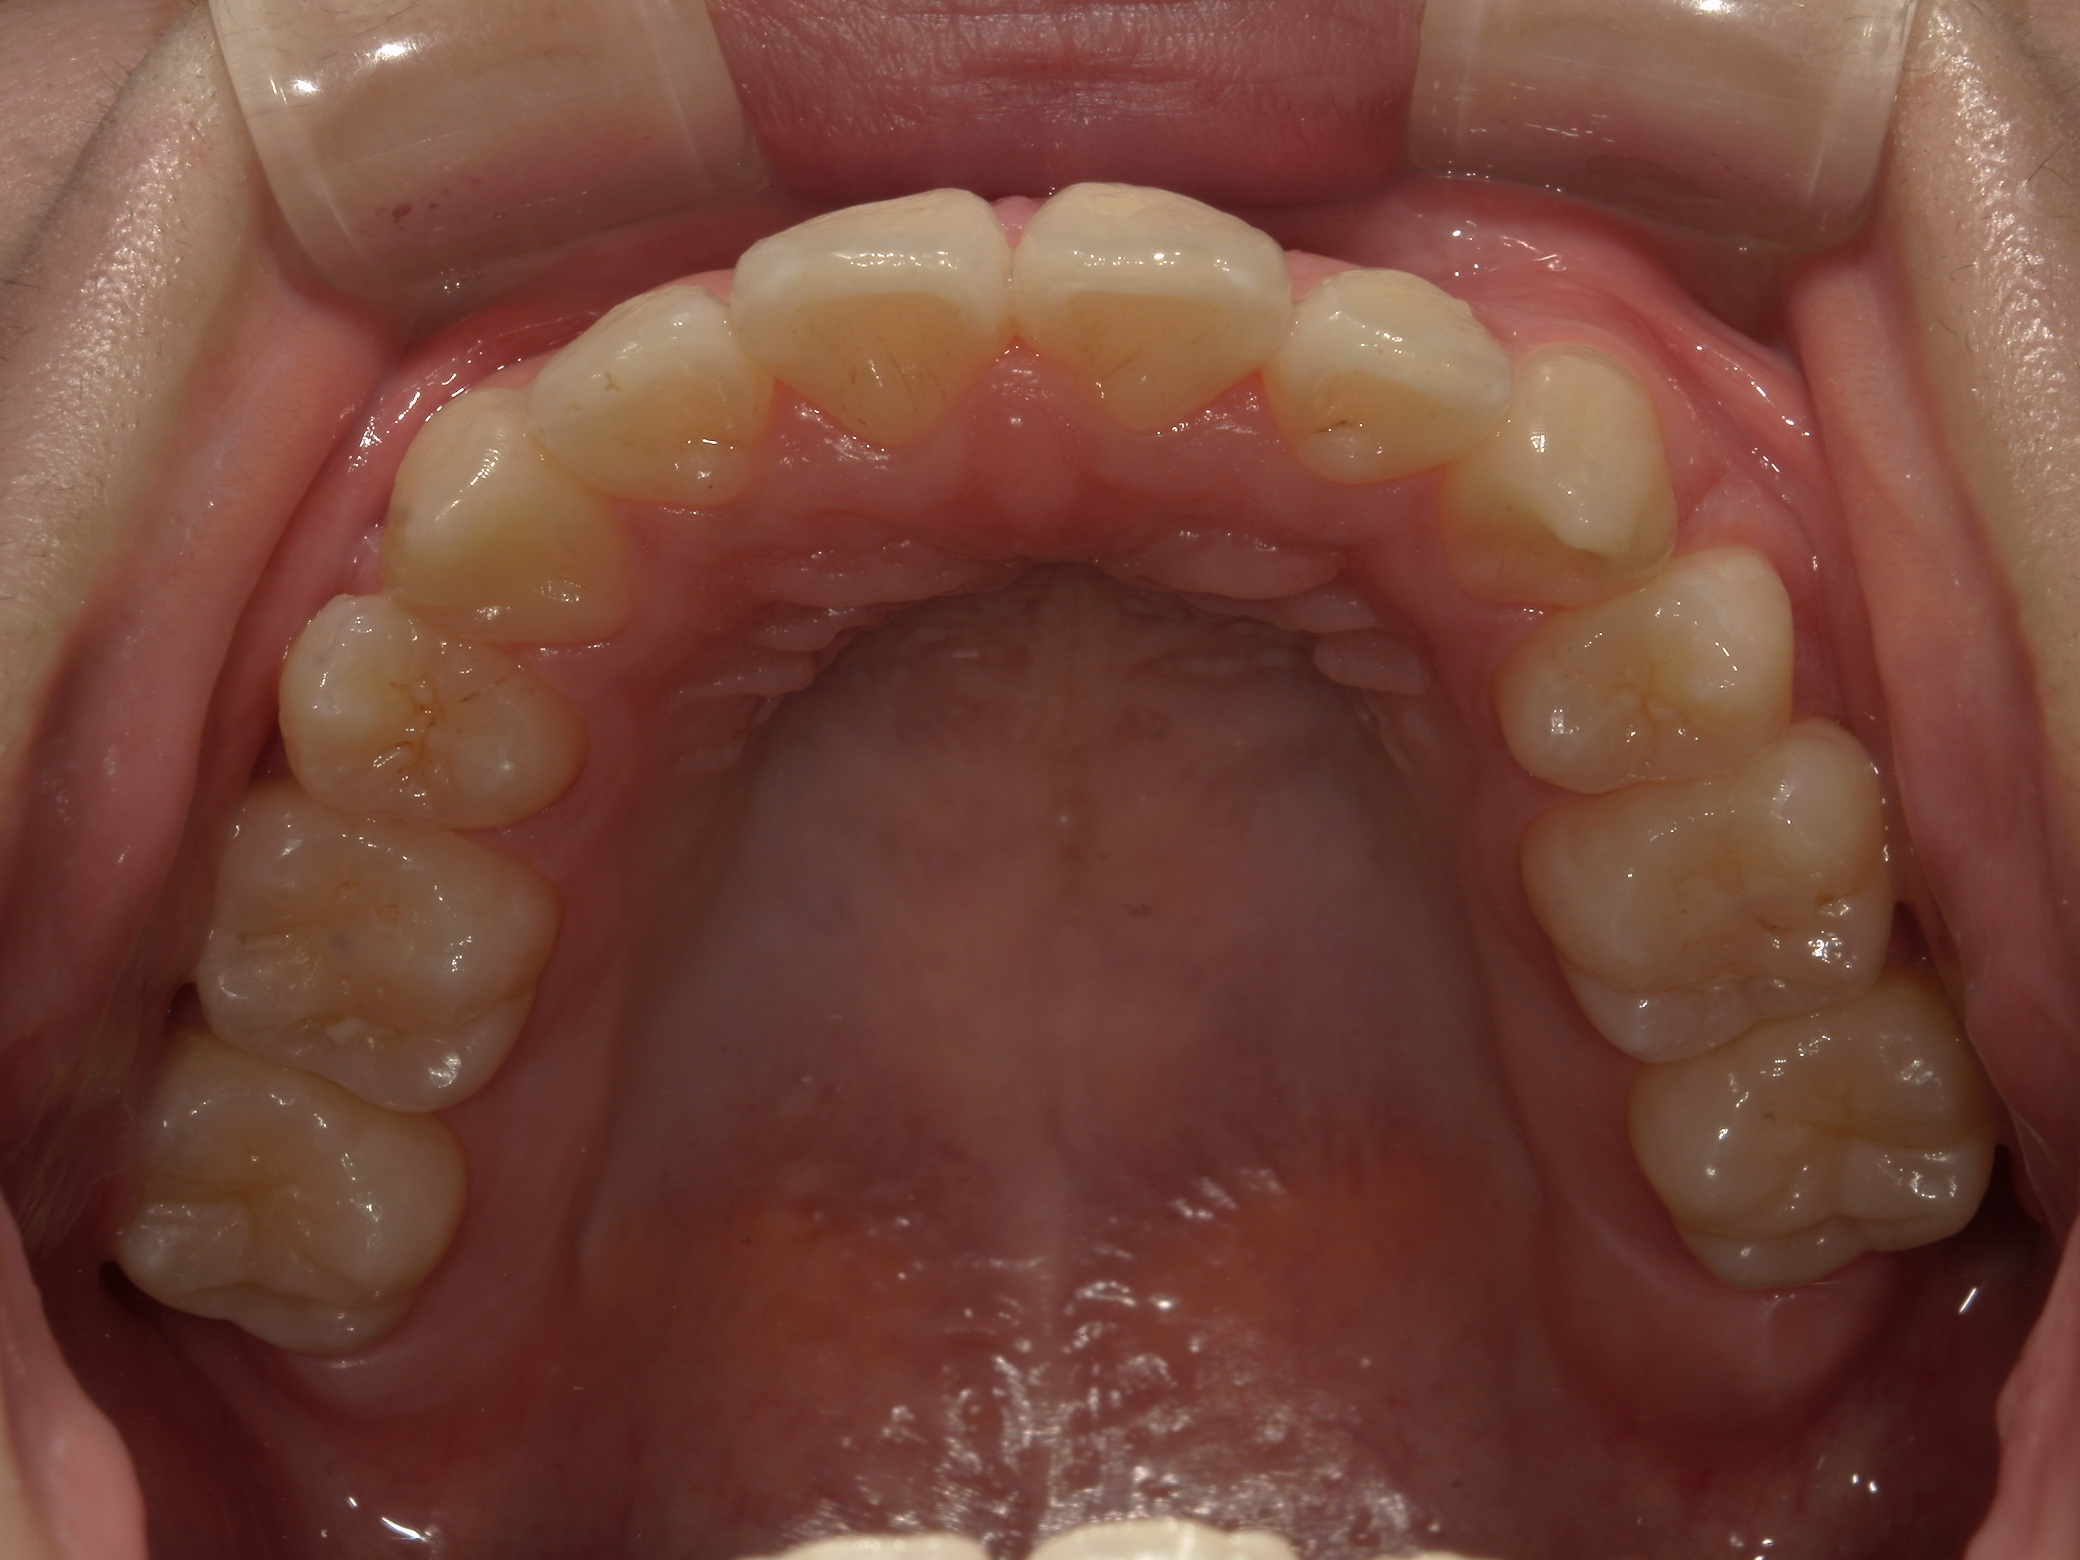

叢生が気になる

| 年齢・性別 | – |

|---|---|

| 主訴 | 叢生が気になる |

| 治療期間・回数 | 1年9ヶ月 |

| 費用 | 1,011,000円 |